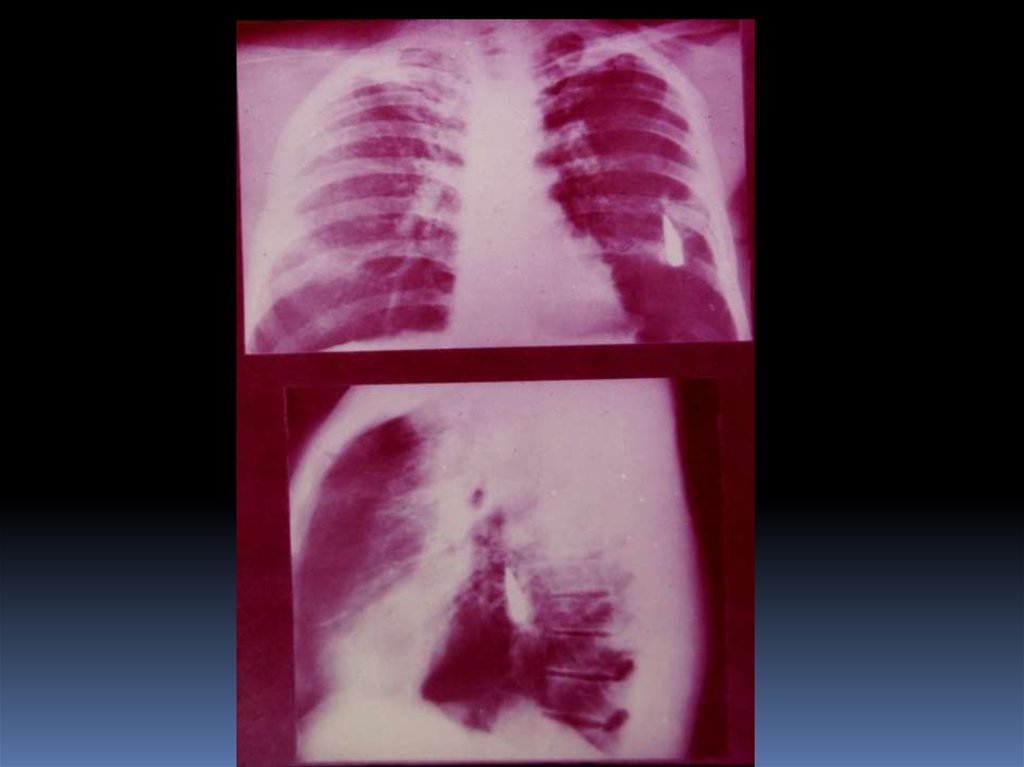

5. Проведение рентгеноскопического исследования раненого.

6. Проведение рентгенографического исследования раненого.

7. Виды травматического повреждения грудной клетки:

пневмоторакс;

гемоторакс;

гемопневмоторакс;

внутрилегочные гематомы;

дисковидные ателектазы;

посттравматические пневмонии.